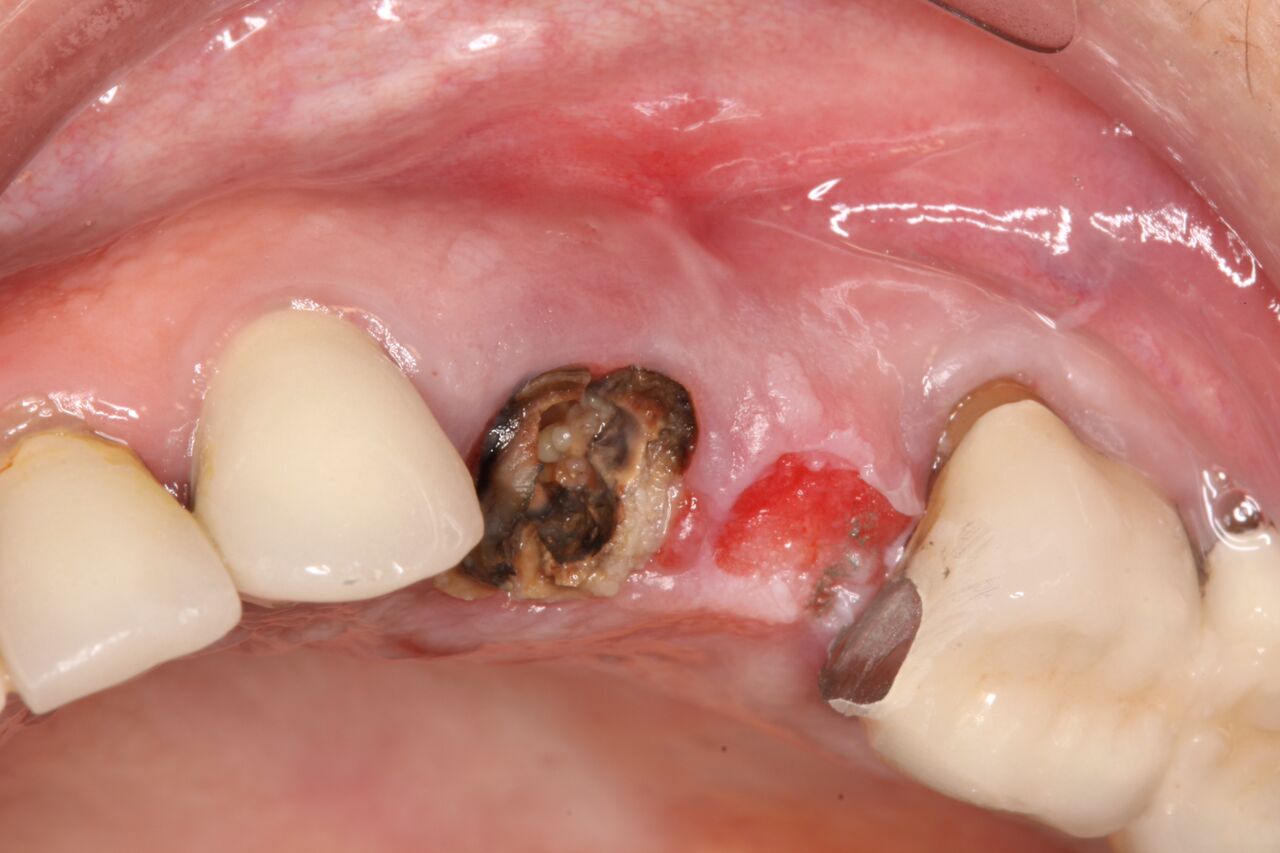

(10.) Initial clinical evaluation of Nos. 12 through 14 after crown on No. 12 and pontic on No. 13 removed.

Figure 10

(11.) Extraction of fractured and decayed No. 12 with periapical granuloma and original

Figure 11

(12.) Extraction of fractured and decayed No. 12 with periapical granuloma and original

Figure 12

A 67-year-old woman presented on an emergency basis with a bad odor and taste from crown No. 12, which had been diagnosed that day at hygiene recall as decayed and no longer attached to the underlying root (Figure 8 and Figure 9). The patient was anesthetized and the existing bridge was sectioned (Figure 10), leaving crown No. 14 intact. The No. 12 root was extracted and the site was fully debrided of granuloma. A platform shift implant was stabilized in excess of 45 Ncm in position No. 12, which was prosthetically correct. The soft tissue of pontic site No. 13 was contoured to mimic soft tissue contours of a bicuspid and an implant was secured in excess of 45 Ncm. Implant No. 13 was milled to allow for unimpeded seating of the temporization abutment, whereas implant No. 12 did not need milling as it was a platform-shift implant. The existing crown No. 12 and cantilever No. 13 were revised to be a temporary bridge on Nos. 12 and 13 (Figure 11 and Figure 12). The revised temporary bridge was positioned in infraocclusion and cemented after the extrusion of excess cement extraorally (Figure 13). No bone graft or sutures were placed as the temporary crowns sealed the sockets.